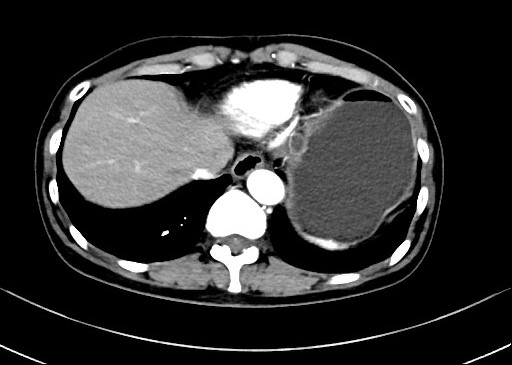

患者,66岁,女性,平素身体健康,以“发现胃肿物2年余”主诉入院,既往于外院行电子胃镜检查发现胃底隆起,直径约1.5-2.0cm,超声内镜检查考虑黏膜下来源间质瘤可能,不除外壁外病变压迫。外院CT提示胃底浆膜下囊性病变可能。患者及家属诊治心切,辗转数家医院后为求内镜下治疗遂来二附院。入院后在消化内科再次超声内镜检查,提示胃壁增生病变可能,增强CT提示胃底胃壁增厚,结合内镜检查。患者及家属强烈要求内镜下探查及病变切除术。术前在王进海主任的指导组织下,进行了专业组内及多学科讨论,与患者及家属充分沟通后,决定行内镜下切开探查及病变治疗术,必要时可行内镜-腹腔镜联合手术(LECS)。邹百仓教授带领内镜下肿瘤诊治及超级微创手术团队施行手术,术中逐层切开胃壁黏膜层及黏膜下层,暴露固有肌层,未发现胃壁病变,遂切开胃壁全层,局部腹腔探查,切口附近腹腔内似韧带组织上发现半球形隆起,表面透亮光滑,大小约1.5X1.5cm,术中请外科李军辉及袁庆攻教授会诊后确诊为囊性病变,讨论后建议可以观察或内镜切开引流,与患者家属沟通后家属强烈要求切开引流,遂用内镜切开刀切开囊肿,引流少量清亮囊液,囊肿塌瘪,观察囊肿切口及局部无出血,切除局部部分胃壁组织送检,内镜下严密关闭切口,留置胃管后,返回病房,常规对症治疗1周,患者无并发症发生,正常出院。

上腹部增强CT 超声内镜